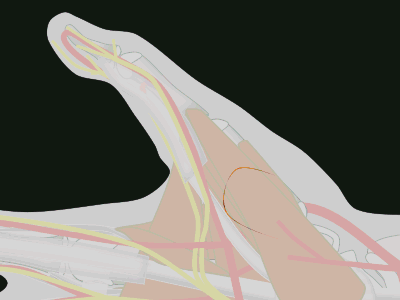

| A key issue is orienting the base of

the flap so that the flap comes to lie perpendicular

to the recipient site. This is best planned

in reverse using a template. This is helpful to also

plan the orientation change resulting from donor site

closure. |

| In this design,

The donor defect is closed as a transposition flap,

making best use of transverse skin laxity in this

area. This rotates the final flap orientation. |

| The goal is to

position the flap against the recipient bed without

tension or torsion. In addition to proper alignment, two key points are: ¤ Adduct the thumb basal joint to bring the flap to the finger to reduce flap tension. ¤ Flex the finger MCP joint to reduce PIP flexion. |